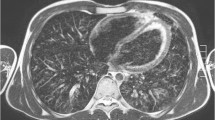

All MR scans were of diagnostic quality despite the fact that the examinations were complicated by coughing and irregular breathing (Fig. 1). Motion artifacts were present on all MRI scans; these, however, were only barely visible (i.e., low) in eight and moderate in seven cases. The artifacts were mainly ghosting artifacts of the chest wall. In case folding artifacts as a result of the parallel imaging, pulsation artifacts and inhomogeneous fat saturation occurred, they did not interfere with the assessment.

While protocols for CT examinations of the lung are nowadays largely standardized, this is not the case for MRI. Based on our experience at 1.5 T, we used a cardiac and respiratory-gated T2-weighted turbo spin echo sequence (T2w-TSE) for the study: This technique is very robust towards the susceptibility artifacts, which are expected to be more pronounced at high-field MR [13, 14]. In addition, this sequence provides high contrast between active pathological and healthy lung parenchyma (Fig. 2). We used fat suppression, as we employ it in our whole body screening protocols.